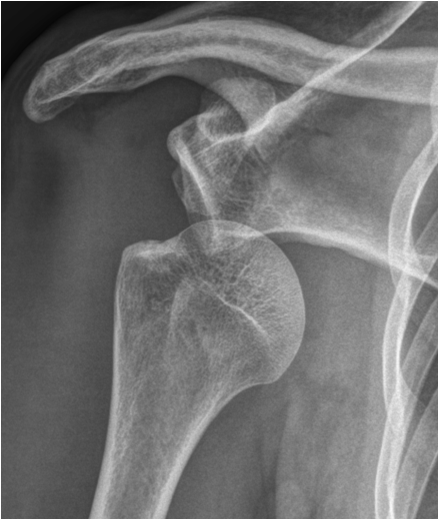

Fig. 12. A) Complete dislocation with contraction in the elbow joint. Ulna and radius are both dislocated and dorsally displaced. B.) Anterior and inferior dislocation of the humerus.

Fig. 13. A) Knee joint with degenerative changes. Note the sclerotic medial tibial plateau and joint space narrowing. A small osteophyte is seen on the medial femoral condyle. B.) Pelvis with marked degeneration of both hip joints. The right femoral head shows lateral osteophyte formation and is deformed. The joint space is narrow with increased subchondral sclerosis of the acetabular roof. The left hip has a marked joint space narrowing and lateral osteophyte formation. The femoral head shows increased density due to sclerotic areas and irregularity.